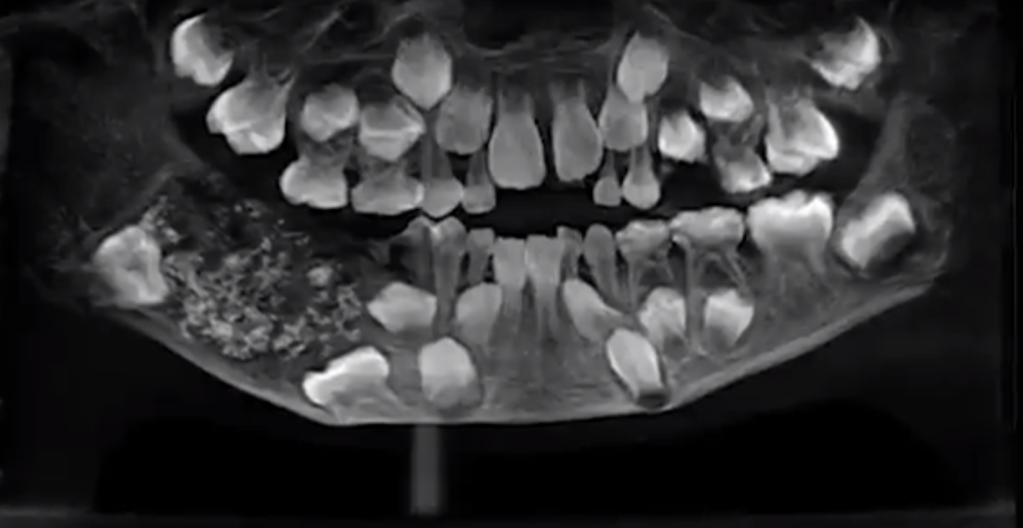

When doctors scanned and x-rayed his mouth, they found a sac embedded in his lower jaw filled with “abnormal teeth,” Dr. Prathiba Ramani, the head of Oral and Maxillofacial Pathology at Saveetha Dental College and Hospital, told CNN.

“There were a total of 526 teeth ranging from 0.1 millimeters (.004 inches) to 15 millimeters (0.6 inches). Even the smallest piece had a crown, root and enamel coat indicating it was a tooth,” she said.